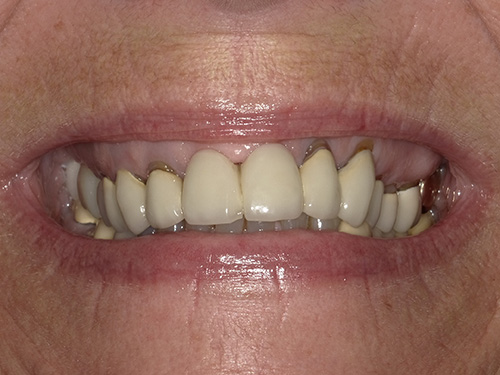

All photos shown below are real patients treated by Dr. Flex — no stock images here. Hover over each image to view the “before” photo and see the amazing results for yourself.